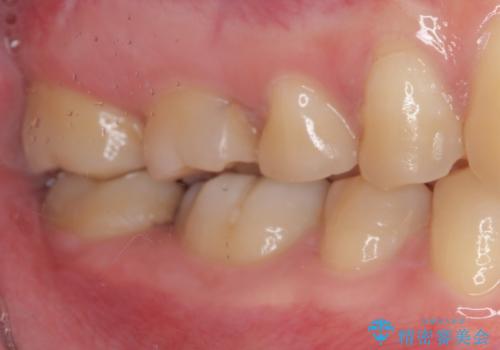

- 矯正治療後に目立つ銀歯を白くしたいとのことで来院された患者様です。

右下の銀の詰め物は、外してむし歯を除去した後、セラミックインレーにて修復することとしました。

左上の銀歯は、銀歯の下に金属の土台が入っているため、その土台を除去し、ファイバーコアにやり替えて、オールセラミッククラウンにて補綴することとしました。

適合の良いセラミック治療は、むし歯再発のリスクが低いです。

目立つ銀歯がなくなり、患者様は大変満足されました。